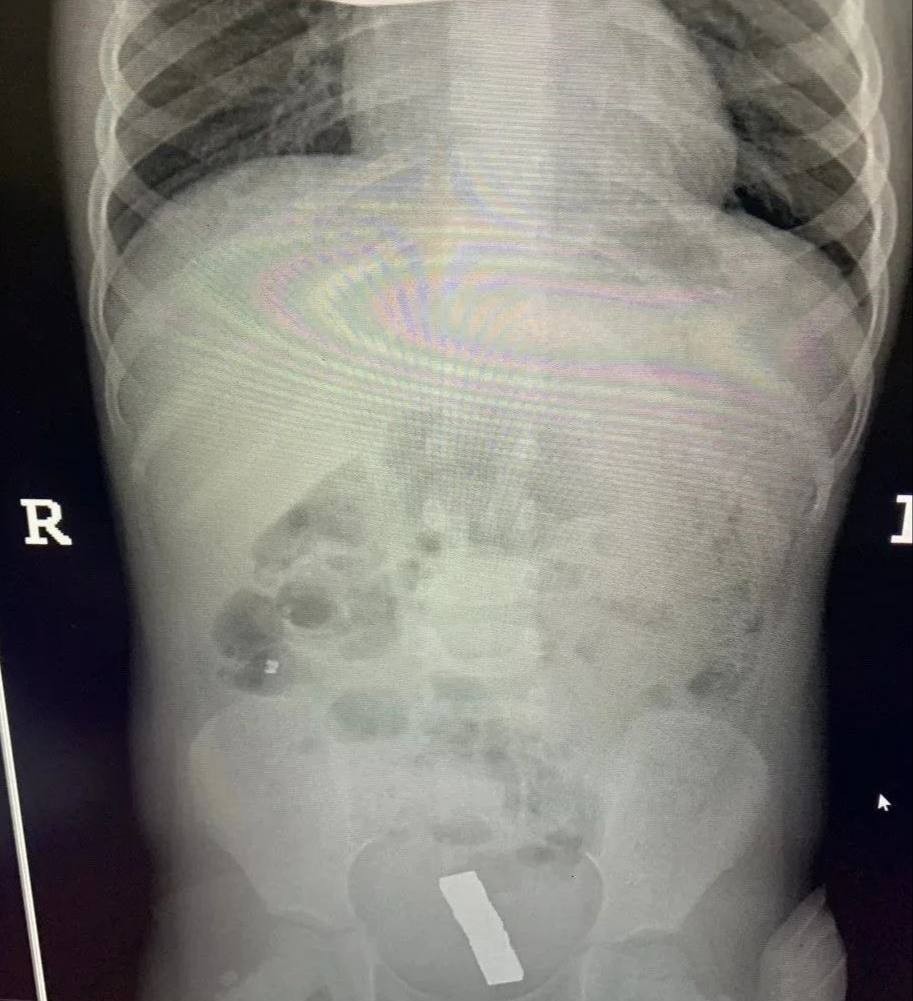

Инцидент произошел в Балашихе — малолетнюю пациентку с жалобами на острую боль в животе доставила в больницу бригада скорой помощи. Обследование показало, что внутри у ребенка большое количество металлических инородных тел. Девочку немедленно отправили на операционный стол.

Врачи приняли решение обойтись без полостного вмешательства. Через крошечные проколы специалисты аккуратно извлекли 20 магнитов из организма ребенка — они успели притянуться друг к другу и прожечь стенку кишки насквозь. Пять штук и вовсе мигрировали в область малого таза.

Хирурги зашили ребенку перфорированный кишечник. Девочка быстро оправилась и уже выписана домой.